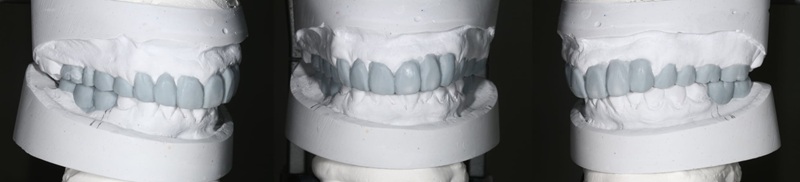

ワックスアップ

こちらがワックスアップと呼ばれる最終的な仕上がりをシュミレーションした状態です。

そして下の奥歯の歯がないところには、インプラント入れる計画を立てました。